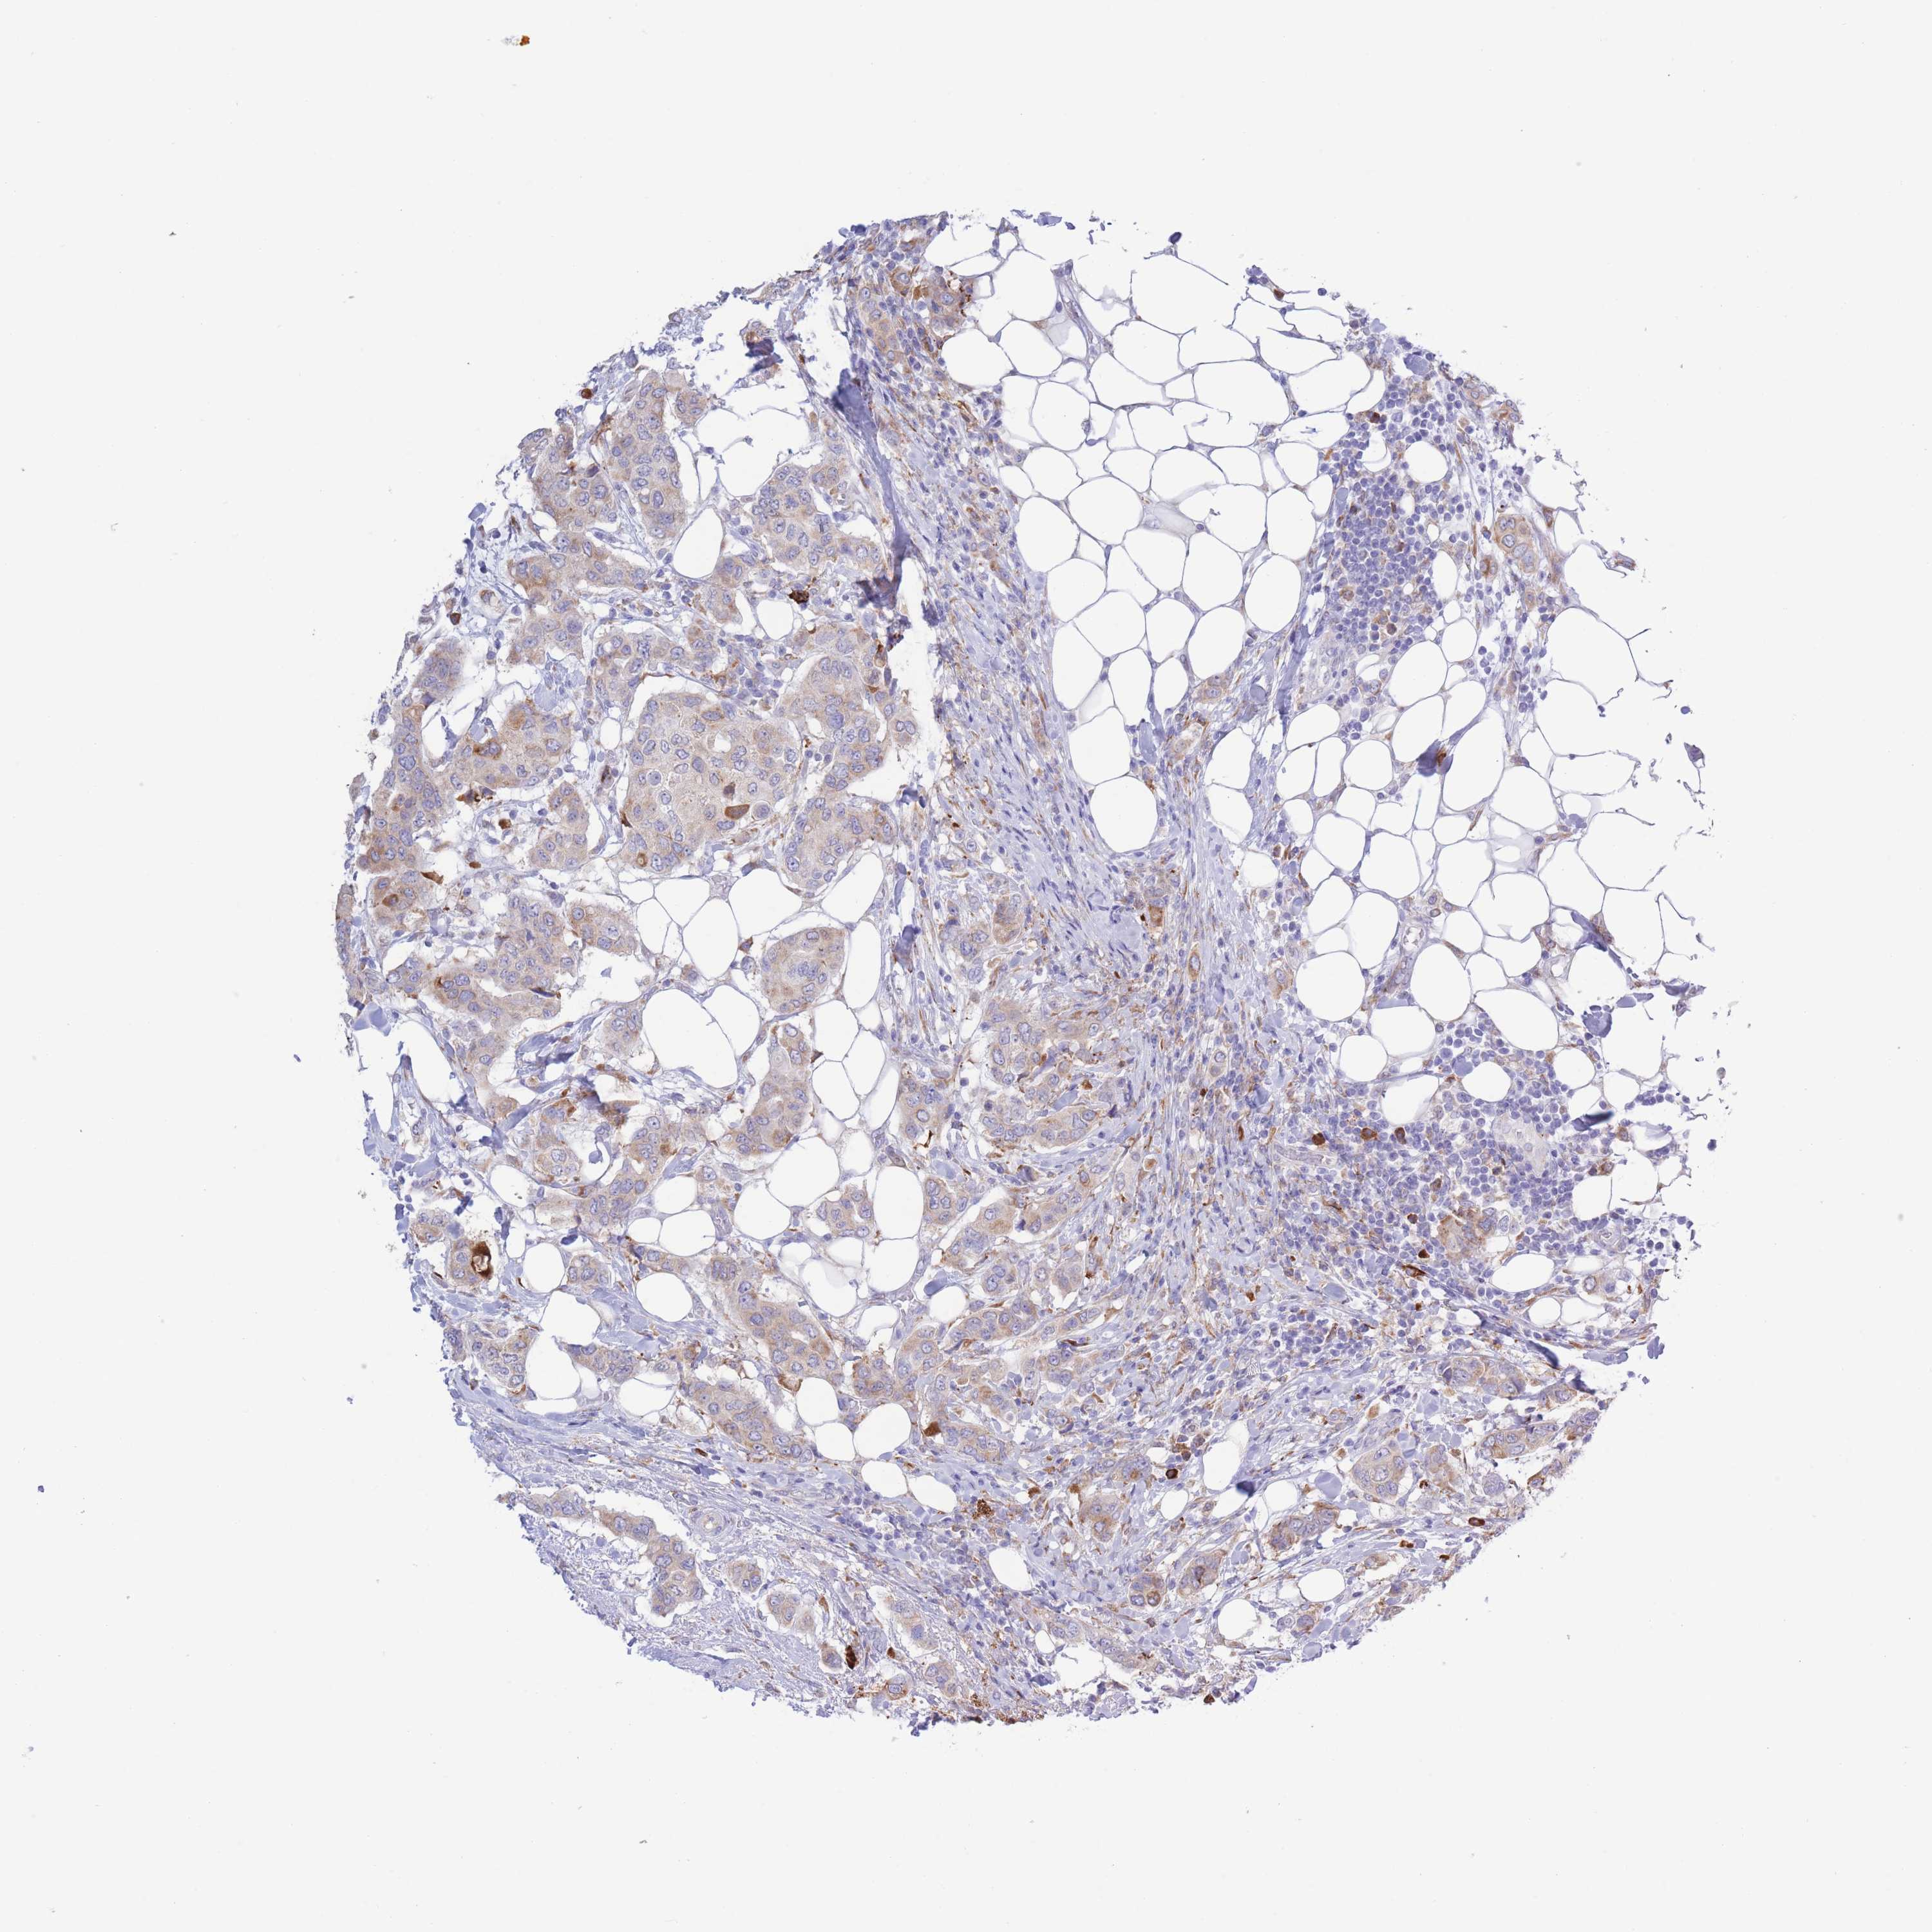

CANCER BREAST CANCER Show tissue menu

BRCA TCGA BRCA VALIDATION PROTEIN EXPRESSION